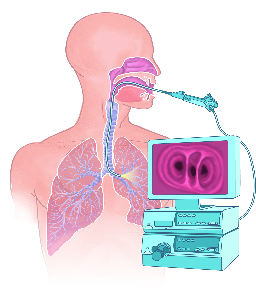

Detailreiche Fotografien aus der medizinischen Praxis ergänzen die Texte; moderne, genaue,

wissenschaftliche Zeichnungen geben Einblick in die Anatomie und die Funktion der Lunge und

anderer Organe.